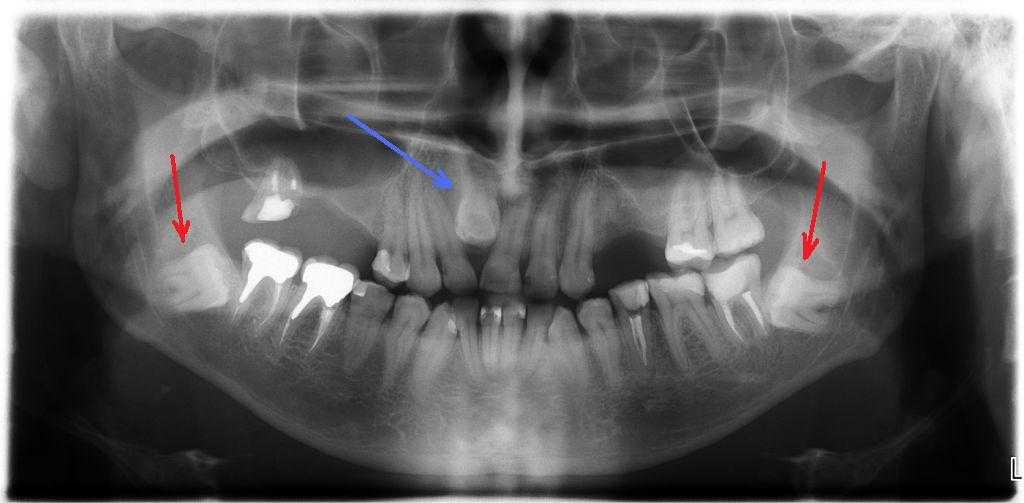

Зуб мудрости – это генетическое отклонение. А вот это и есть атавизм, нашим предкам крепкие коренные зубы помогали перетирать растительную пищу. Мы бы и сейчас могли ими жевать, но в большинстве случаев растут они неправильно, чем доставляют массу неудобств и приводят человека к хирургу-стоматологу.

Зуб мудрости

По сравнению с нашими предками у современного человека гораздо меньшая по размеру челюсть. Поэтому для так называемых «восьмерок», или зубов мудрости , просто не хватает места. Раньше же эти зубы позволяли пережевывать нашим предкам жесткую и твердую пищу. Современный человек потребляет обработанные каким-либо образом продукты, поэтому необходимость в этих зубах пропала.

У многих людей зубы мудрости никогда не выпростают, но это не значит, что их нет

Зубы мудрости (они же моляры) помогали нашим предкам измельчать твердую пищу, но сейчас мы едим преимущественно «мягкие» продукты. Да и сам процесс жевания несколько изменился и сместился ближе к клыкам. Интересно, что зубы мудрости есть не у всех — их наличие зависит от генетической предрасположенности конкретного человека.

Зубы мудрости —

это самые запоздалые и строптивые костные образования ротовой полости. Изначальная функция состояла во вспомогательном процессе пережевывания твердой, жесткой пищи.

Современная трапеза людей больше включает термически обработанные продукты, поэтому в ходе эволюции орган атрофировался. Расположенные последними в ряду, зубы мудрости часто вылезают у людей в сознательном возрасте. Распространенным явлением служит отсутствие «восьмерок», частичное прорезывание.

Зубы мудрости

Это восьмые зубы в зубном ряду, в простонародье именуемые восьмеркой. Как известно, свое название «восьмерки» получили в связи с тем, что прорезаются значительно позже остальных зубов — в среднем в возрасте от 18 до 25 лет (у некоторых людей не прорезаются вообще). Зубы мудрости считаются рудиментами: в свое время они были необходимы нашим предкам, но после того как рацион питания Homo sapiens значительно изменился (уменьшилось потребление твердой и жесткой пищи, люди стали употреблять еду, подвергшуюся термической обработке), а объем мозга увеличился (вследствие чего природе «пришлось» уменьшить челюсти Homo sapiens) — зубы мудрости решительно «отказываются» вписаться в наш зубной ряд.

Эти «хулиганы» среди зубов то и дело норовят вырасти вкривь и вкось, из-за чего изрядно мешают другим зубам и общей гигиене полости рта: вследствие неправильного расположения «восьмерок» между ними и соседними зубами то и дело застревает пища. Да и зубной щетке добраться до зубов мудрости не так-то просто, поэтому их часто поражает кариес, что приводит к удалению больного зуба. Однако при правильном расположении зубов мудрости они, к примеру, могут служить опорой для мостовидных протезов.